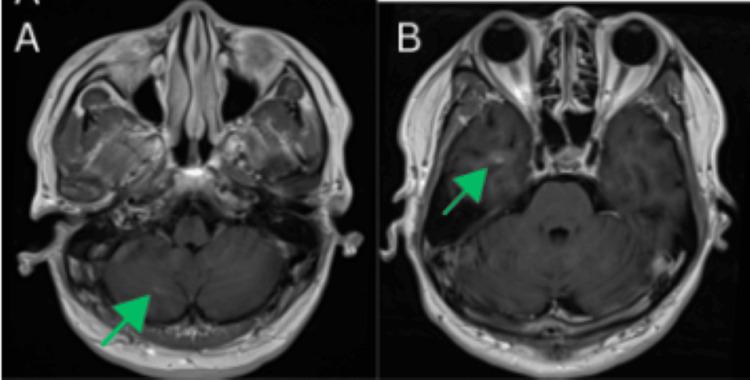

Lung cancer remains the leading cause of cancer-related deaths globally. While smoking-related lung cancers still account for most cases and cause approximately 100,000 deaths annually in the USA, smoking rates have been declining for decades. Lung cancer in never-smokers (LCINS), which tends to affect women and Asian populations, is now the fifth most common cause of cancer-related deaths worldwide. In 2023, over 20,000 lung cancer deaths in the USA were projected to occur in never-smokers, making LCINS the eighth leading cause of cancer-related mortality in the country. As the number of LCINS cases rises, it becomes increasingly important to explore the unique causes and characteristics of the disease, which calls for tailored diagnostic approaches and personalized treatment plans. Lung adenocarcinoma (LUAD) can present with atypical imaging features that often resemble benign conditions, including pneumonia, lung abscesses, post-infectious scarring, atelectasis, mediastinal masses, emphysema, and granulomatous disease. This variability in presentation can hinder accurate diagnosis and potentially delay timely treatment. While lung cancer is uncommon in younger individuals, with only 5.6% of new cases occurring in those under 54 years old, clinicians should maintain a high index of suspicion, as early detection is essential, and atypical cases can be easily missed. Here, we present a complex case involving an unusual radiologic manifestation of a lung mass, in which tuberculosis was initially considered the primary differential diagnosis.

肺癌仍然是全球癌症相关死亡的主要原因。虽然与吸烟相关的肺癌仍然占大多数病例,并且在美国每年导致约10万例死亡,但吸烟率几十年来一直在下降。从不吸烟者中的肺癌(LCINS),往往影响女性和亚洲人群,现在是全球癌症相关死亡的第五大常见原因。2023年,预计美国超过2万例肺癌死亡将发生在从不吸烟者中,使LCINS成为该国癌症相关死亡率的第八大原因。随着LCINS病例数量的增加,探索该疾病的独特病因和特征变得越来越重要,这需要量身定制的诊断方法和个性化的治疗方案。肺腺癌(LUAD)可能表现出非典型的影像学特征,这些特征通常类似于良性疾病,包括肺炎、肺脓肿、感染后瘢痕、肺不张、纵隔肿块、肺气肿和肉芽肿性疾病。这种表现的变异性可能会阻碍准确诊断并可能延迟及时治疗。虽然肺癌在年轻人中并不常见,只有5.6%的新病例发生在54岁以下的人群中,但临床医生应保持高度的怀疑指数,因为早期检测至关重要,非典型病例很容易被漏诊。在此,我们介绍一个复杂病例,涉及肺部肿块的不寻常放射学表现,其中最初将肺结核视为主要鉴别诊断。